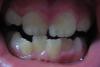

Nad Опубликовано 20 августа, 2008 Автор Поделиться Опубликовано 20 августа, 2008 Вот фото зубов моего ребенка. Что посоветуете? Ссылка на комментарий

Dr.INGa Опубликовано 21 августа, 2008 Поделиться Опубликовано 21 августа, 2008 Вот фото зубов моего ребенка. Что посоветуете?По этой фотографии можно только понять,что у ребёнка есть дефицит места для прорезывания постоянных зубов на обеих челюстях. Пожалуйста,сфотографируйте зубы в сомкнутом состоянии(не смещая при этом нижнюю челюсть вперёд или в сторону)-вид слева,справа и спереди. Ссылка на комментарий

Nad Опубликовано 22 августа, 2008 Автор Поделиться Опубликовано 22 августа, 2008 По этой фотографии можно только понять,что у ребёнка есть дефицит места для прорезывания постоянных зубов на обеих челюстях. Пожалуйста,сфотографируйте зубы в сомкнутом состоянии(не смещая при этом нижнюю челюсть вперёд или в сторону)-вид слева,справа и спереди.Спасибо за ответ. Завтра размещу нужные фото. На этой фото ребенок действительно выдвинул челюсть вперед Ссылка на комментарий